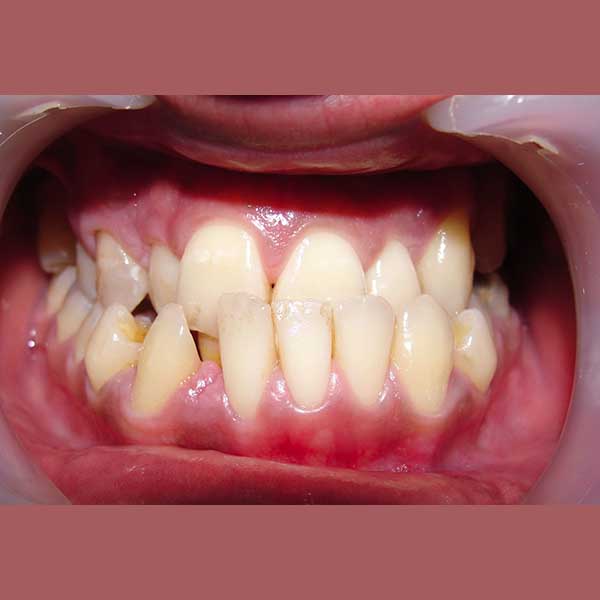

BEFORE

“راجعتني هذه الشابة قبل عدة سنوات وهي تعاني من ازدحام شديد في أسنانها، لدرجة أن أحد أنيابها قد بزغ بشكل مرتفع وبعيد عن مكانه الطبيعي. طلبت مني صديقتنا مساعدتها وترتيب أسنانها ولكن من دون قلع أسنان.